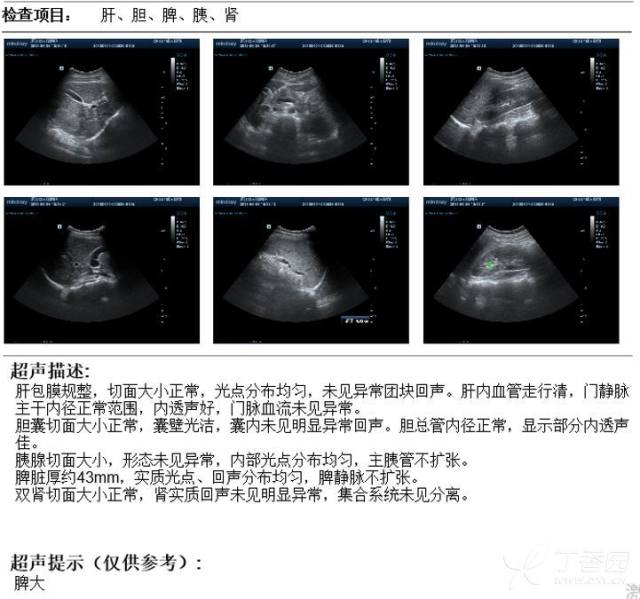

腹腔及腹膜后多发肿大淋巴结,会是什么呢

腹腔及腹膜后多发肿大淋巴结,会是什么呢